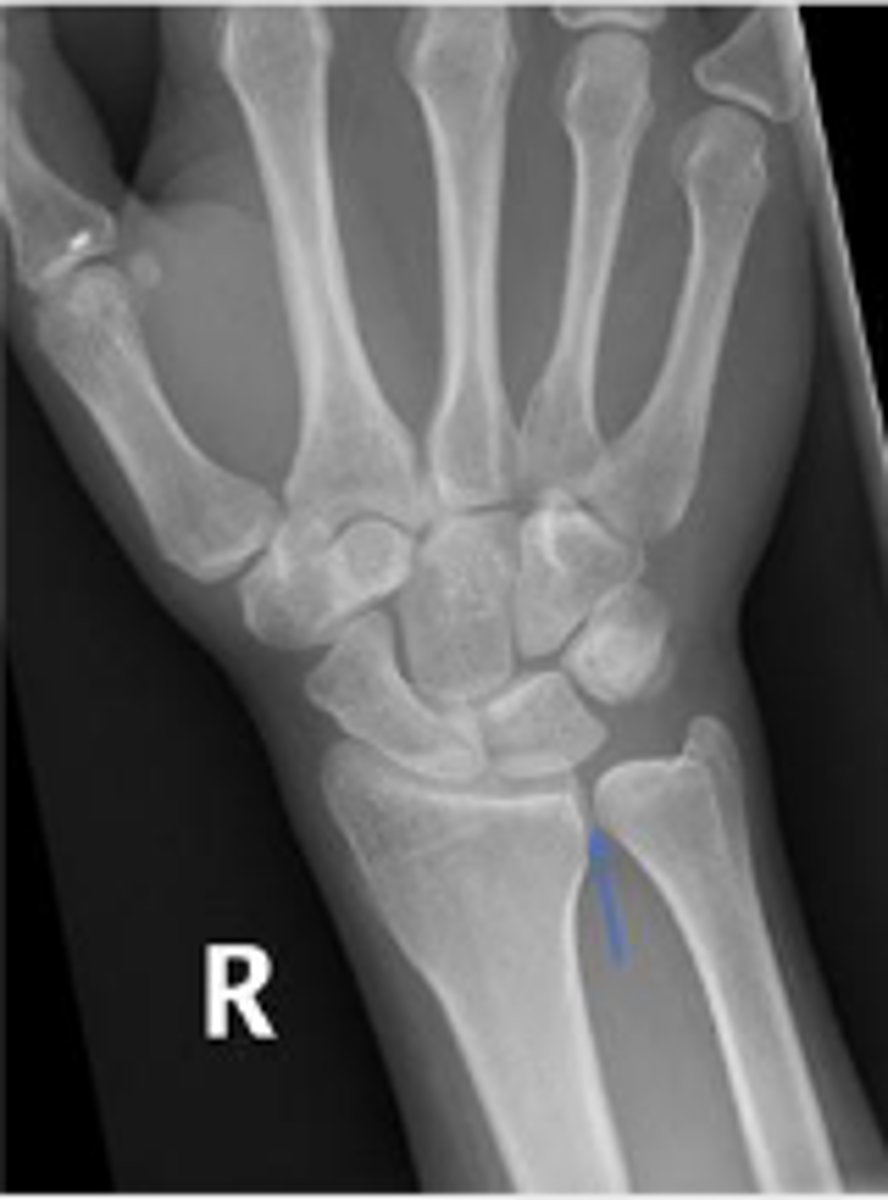

PA right wrist

What is the name of the radiographic view?

3 arcs of carpal alignment

What is the name of the assessment

Proximal cortical aspect of the first (proximal)

carpal row (ARC 1)

What are the landmarks for the most proximal line in the assessment?

Distal cortical aspect of the first (proximal) carpal

row (ARC 2)

What are the landmarks for the most middle line in the assessment?

Proximal cortical aspect of the second (distal)

carpal row (ARC 3)

What are the landmarks for the most distal line in the assessment?

SLAC wrist; carpal dislocation, carpal fracture

Name 2 conditions that will result in an alteration of the assessment?

PA wrist

What radiographic view are the

carpal joint spaces assessed?

1-2mm

What is the normal range for the carpal joint spacing?